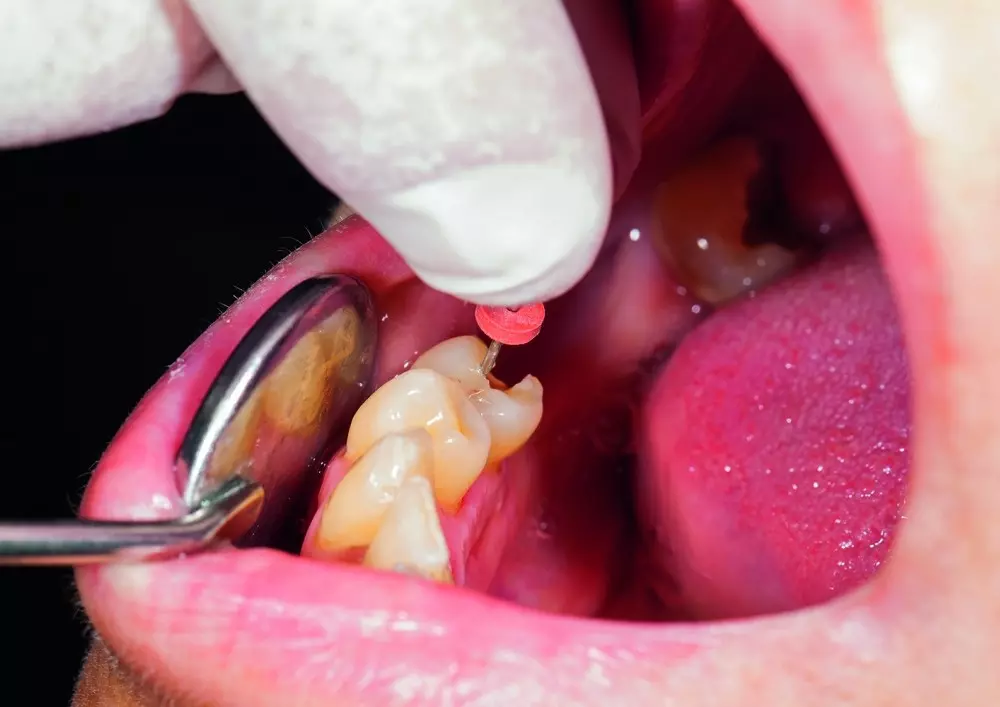

Powtórne leczenie endodontyczne stosuje się w przypadku, kiedy pierwotne leczenie nie przyniosło oczekiwanych rezultatów. Zastosowanie ultradźwięków poprawia jego skuteczność, znajdując zastosowanie m.in. w tworzeniu dostępu do korony, usuwaniu kamieni miazgowych oraz kondensacji gutaperki. Więcej na temat powtórnego leczenia endodontycznego z zastosowaniem ultradźwięków pisze lek. stom. Adam Romaniuk-Demonchaux.